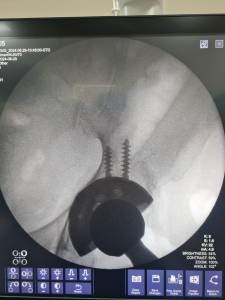

A young man with previous history of Panner’s disease presented at our clinic. The patient experienced a locking sensation in his elbow during movement. No obvious deformity such as an osteochondrosis was observed via X-ray imaging. However, during clinical examination, the orthopaedic team noted a disturbance during movement in the joint. After consideration of the patient’s history, we decided to perform a surgical exploration, during which the osteochondral fragment was successfully identified and removed. Panner’s disease, which refers to osteochondrosis of the capitellum of the humerus, is observed in children between ages 4 to 10, and is typically self-limiting. In this particular individual, the disease was not resolved; instead, the osteochondrosis remained loose in the joint, creating a locking sensation in the joint during movement.